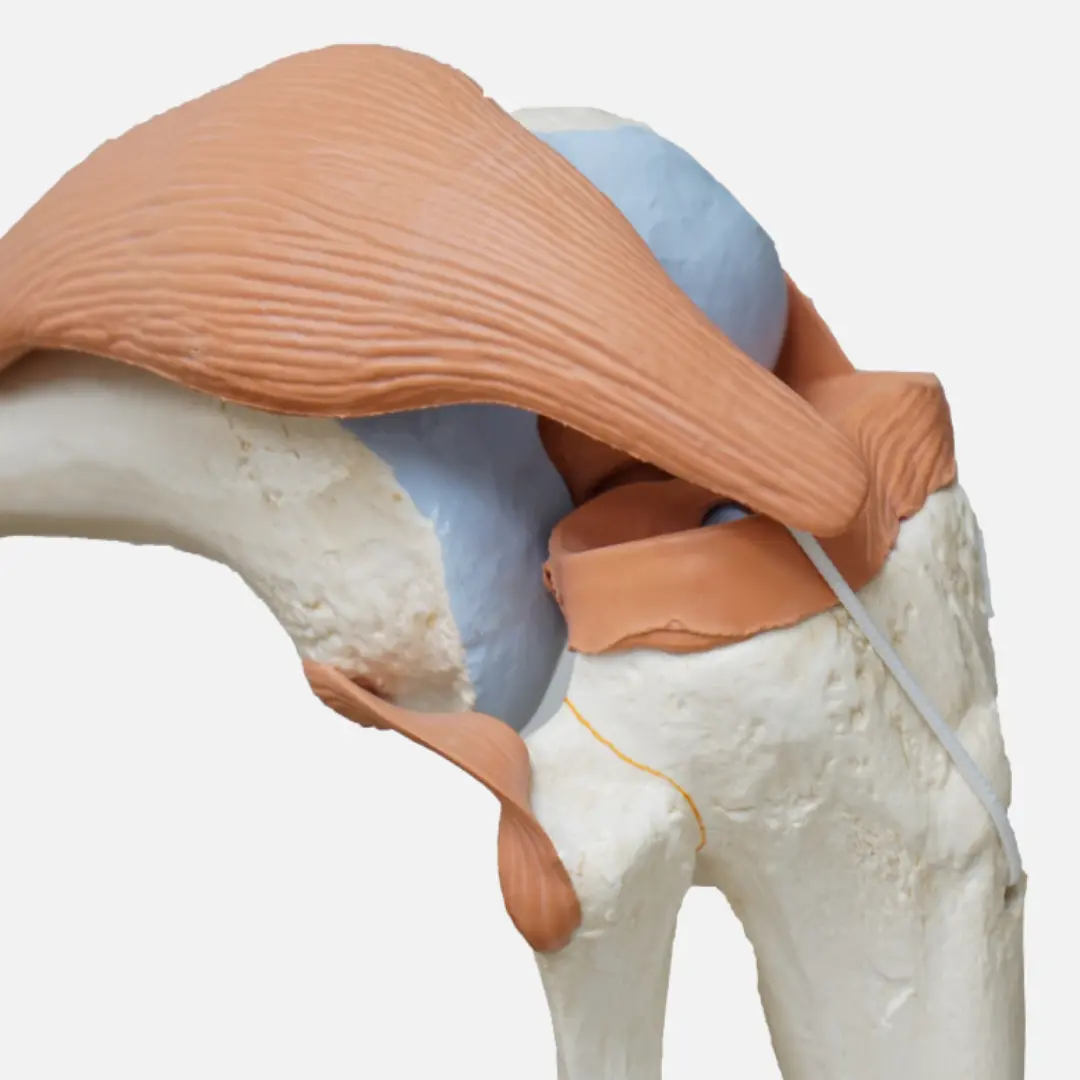

십자인대 파열은 무릎 관절 내에 위치한 중요한 인대인 전방 십자인대(ACL) 또는 후방 십자인대(PCL)가 손상되어 발생하는 부상이에요. 주로 스포츠 활동 중 갑작스러운 방향 전환, 급격한 감속, 무릎에 가해지는 직접적인 충격 등으로 인해 발생하며, 파열 정도에 따라 증상이 다르게 나타날 수 있어요.

전방 십자인대 파열 시에는 '뚝'하는 파열음과 함께 심한 통증이 즉시 발생하고, 무릎이 불안정하게 흔들리는 느낌을 받을 수 있어요. 부상 직후에는 무릎이 붓고 움직이기 어려워지며, 시간이 지나면서 통증은 감소하지만 무릎의 불안정감은 지속될 수 있어요.

후방 십자인대 파열은 전방 십자인대 파열보다 발생 빈도는 낮지만, 무릎 앞쪽으로의 직접적인 충격이나 과도한 꺾임 등으로 인해 발생할 수 있으며, 통증과 함께 무릎 뒤쪽의 뻐근함, 무릎을 굽히거나 계단을 내려갈 때 불편함이 나타날 수 있어요.